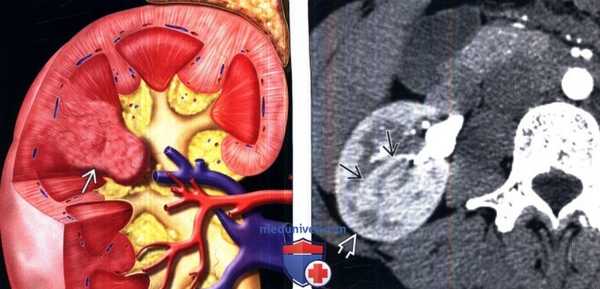

(Слева) На рисунке показано объемное расширение коркового вещества почки между верхней и средней чашечками.

(Справа) КТ, аксиальная проекция, кортико-медуллярная фаза контрастирования: дорсальная половина межполюсной области почки, контрастируемая аналогично корковому веществу почки. На последующих фазах выявлено гомогенное контрастирование почки.